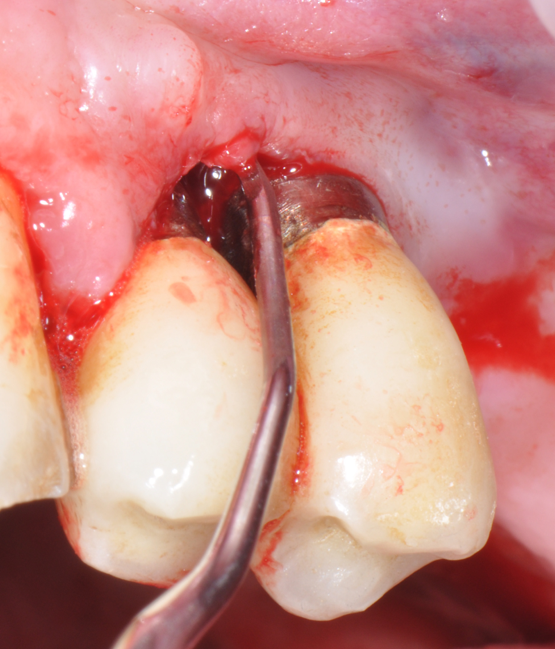

The parameters used to define peri-implant disease usually are: Probing Depth (PD), Crestal Bone Loss (CBL), Bleeding on Probing (BOP) and presence of suppuration and/or fistula.9 Peri-implant mucositis is characterised by soft tissues inflammation witnessed by BOP with or without PD deepening but no effects on the crestal bone while peri-implantitis is characterised by CBL, BOP alone or in conjunction with pus, with or without PD deepening. (Figs. 1, 2 and 3) display the diagnostic steps of a case of peri-implantitis. While mucositis allows a complete healing, peri-implantitis is not reversible.12

Fig.1: Case 1. Peri-implant probing reveals a PPD of 9mm and pus.

Fig.2: Case 1. BOP starts immediately after probing.